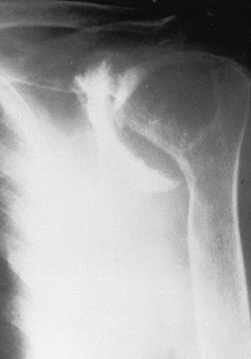

from the severe, unpredictable destruction of both bone and soft

tissue, which is the hallmark of the disease (Fig. 101.51, Fig. 101.52, Fig. 101.53 and Fig. 101.54). Severe medial and superior wear of the

Figure 101.54.

Rheumatoid arthritis with severe bone loss in the proximal humerus. The amount of glenoid bone loss precluded insertion of a glenoid component, and a proximal humeral component alone was used. |